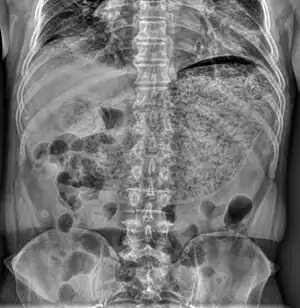

| X-ray showing a large amount of food in the stomach due to severe gastroparesis[1] | |